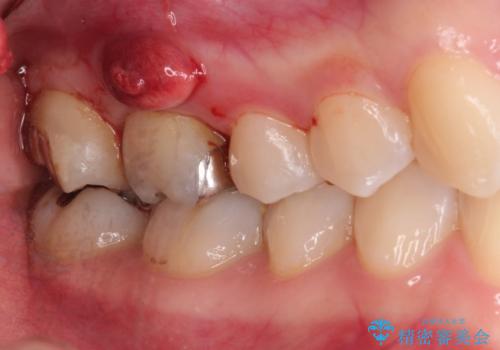

[フルジルコニアクラウン] 老朽化した銀歯を白く

![[フルジルコニアクラウン] 老朽化した銀歯を白くの症例 治療前](https://seimitsushinbi.jp/wp/wp-content/uploads/2020/05/095ef1aef9dfbbc03d4a7b2f7a38a13c-500x350.jpg?v=1588518714)